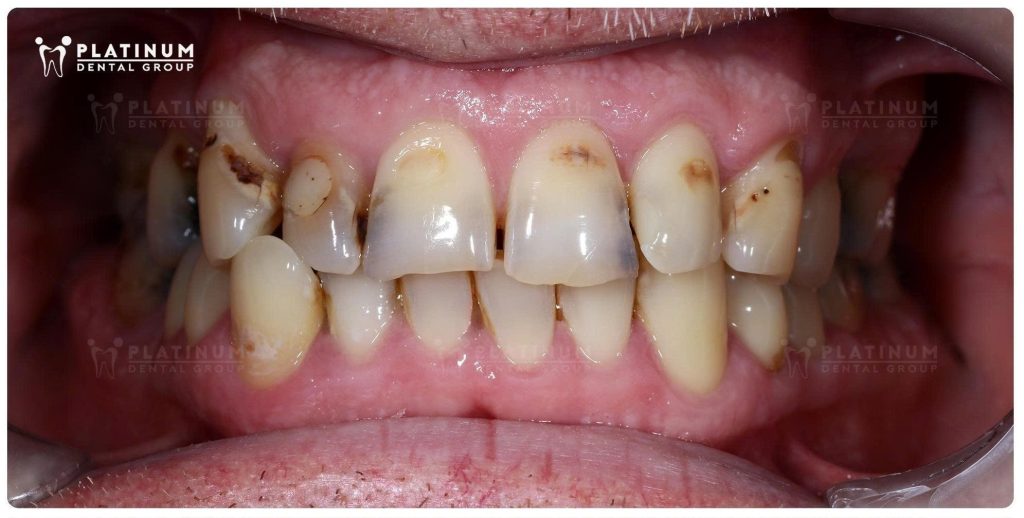

Tình trạng mất răng hàm kéo dài, cùng với các răng còn lại bị sâu và vỡ mẻ, không chỉ ảnh hưởng đến thẩm mỹ mà còn làm suy giảm nghiêm trọng chức năng ăn nhai. Những bữa ăn yêu thích dần trở nên không còn trọn vẹn, và sự tự tin trong giao tiếp cũng theo đó mà thu lại.

Bác sĩ Quốc Duy thực hiện phục hình mão sứ cho các răng sâu, vỡ mẻ lớn của hàm trên đồng thời cân chỉnh lại cung cười.